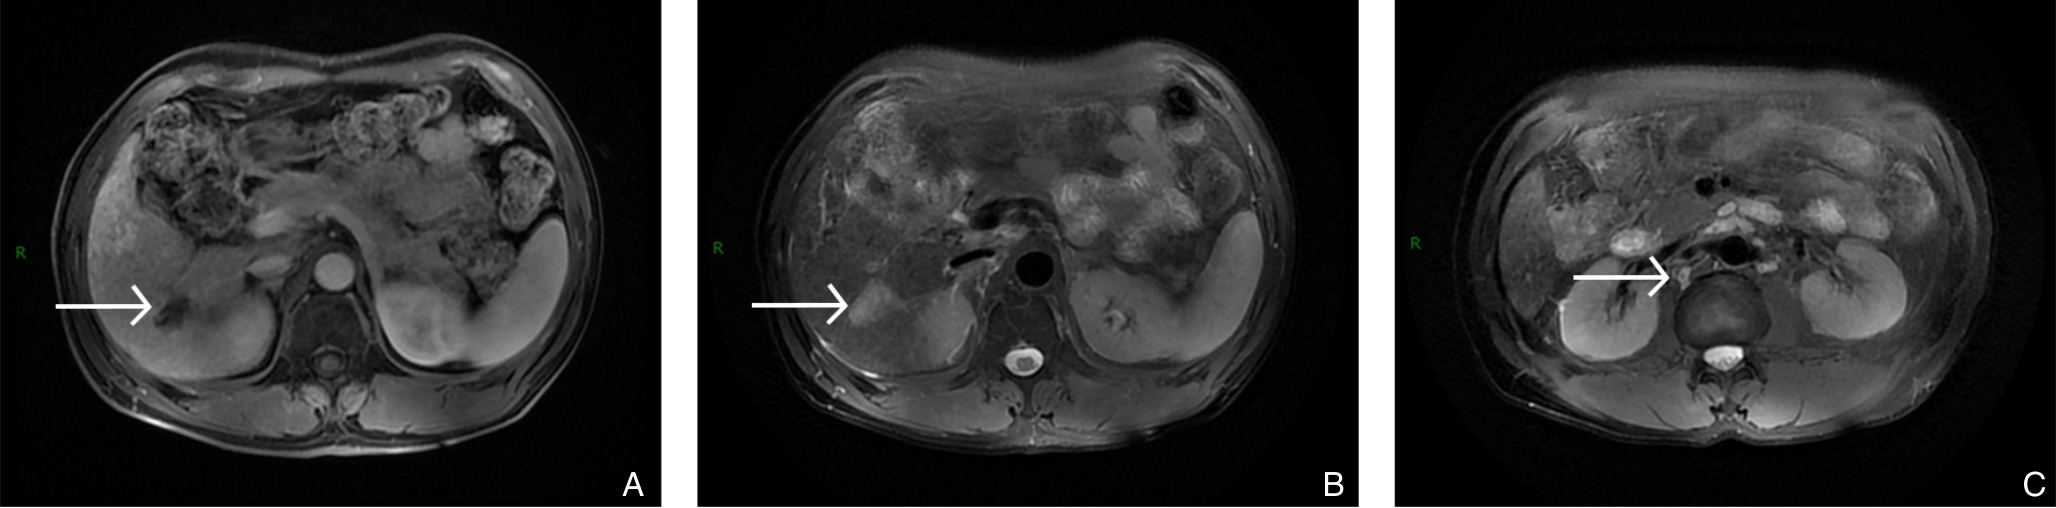

颜可梁,麦伟恒,康钟杰,刘春甫,李作标,刘晓光,陈卫煌,杨永光

2025, 34(8):1783-1789. doi: 10.7659/j.issn.1005-6947.250076

摘要:背景与目的 肝内胆管癌(ICC)是一种起病隐匿、预后极差、初诊多为进展期的原发性肝癌,其治疗选择有限,预后差。本研究旨在探讨靶向治疗、免疫治疗与肝动脉灌注化疗(HAIC)联合应用于晚期ICC的转化治疗的潜力,为临床转化治疗提供参考。方法 回顾广东医科大学附属医院2021年11月收治的1例晚期ICC行靶向治疗、免疫治疗与HAIC联合治疗后成功转化并接受手术患者的诊治过程,并复习国内外相关文献。结果 患者为52岁男性,确诊为T2N1M0-Ⅲb期ICC。患者拒绝接受以吉西他滨联合顺铂为主的一线化疗方案,同意行靶向治疗联合免疫治疗与HAIC的综合治疗,在接受4个治疗周期后评估肿瘤达到部分缓解,具备实施根治性手术治疗的条件。患者随后接受了腹腔镜下肝S6段和部分S7段切除、胆囊切除以及肝门部和腹膜后淋巴结清扫术。术后患者规律行靶向免疫联合化疗的综合治疗方案。在疾病出现复发和转移后,化疗药物进行了相应调整。截至目前,患者无病生存期达15个月,总生存期超过3年。结论 靶向治疗、免疫治疗与HAIC三联方案可提高晚期ICC患者的转化机会并延长生存期,具有较好的安全性和临床应用前景,但其疗效仍需多中心研究进一步验证。